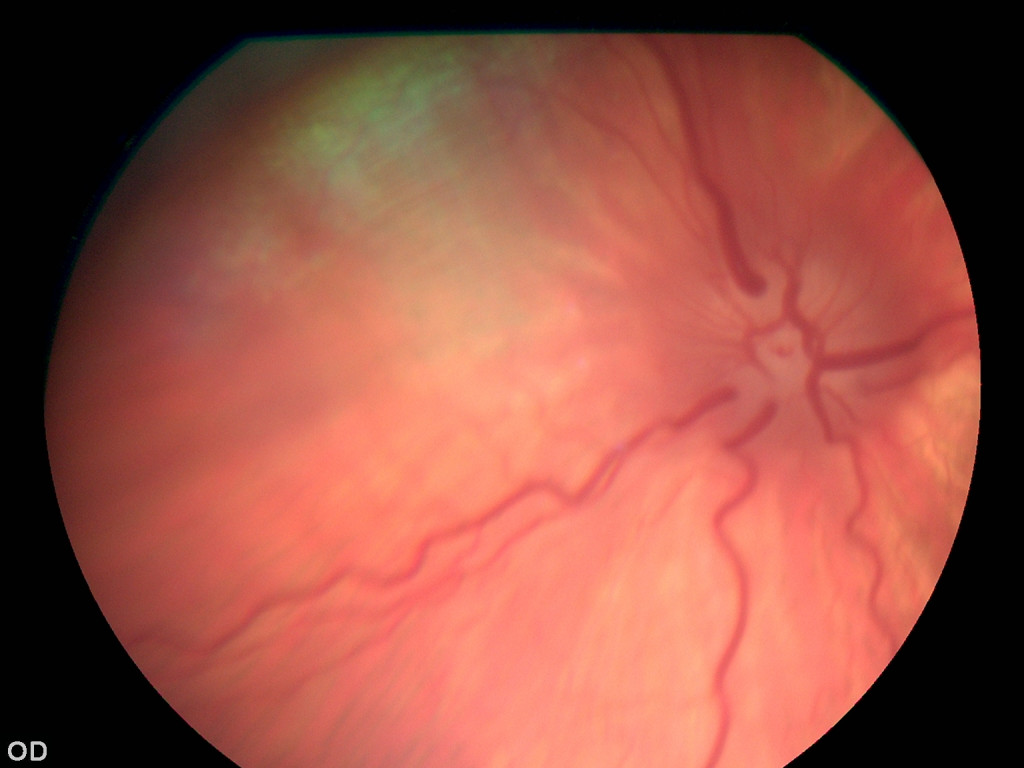

Слепота у животных – это полная или частичная утрата зрительной функции. Она может быть обусловлена патологией глазного яблока, а также патологиями различных структур нервной системы4.Вне зависимости от локализации проблемы слепота может быть приобретенной (фото 1) или врожденной (фото 2).